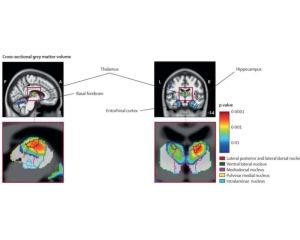

[研究进展] 超长者和老年人大脑结构存在显著差异 日期:2023-08-12 17:03:36 点击:145 好评:0

作者:Justin Jackson , Medical Xpress 灰质体积纵向差异的彩色图,显示随着时间的推移,超长者灰质体积的减少速度慢于典型老年人。组别与时间之间存在显著的交互作用;经误差校正后的P0-05;...